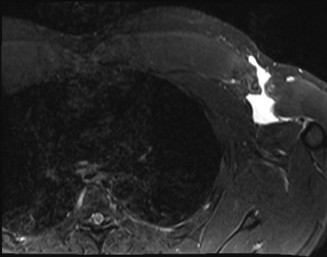

A 24-year-old, male athlete sustains an anterior shoulder dislocation. His MRI is shown in Figure 2–32.

Figure 2–32

The correct answer is (A). The MRI demonstrates an HAGL lesion. The MR arthrogram shows fluid extending down the medial humerus and is indicative of an HAGL. Most commonly, with an anterior dislocation, the anterior band of the inferior glenohumeral ligament is torn. With a posterior dislocation, the posterior band is torn creating a reverse HAGL. The ligament tends to tear off the humeral side. These are important injuries to identify as arthroscopic labral repair and capsular shift may be unsuccessful without concomitant repair of the HAGL lesion. Many authors advocate an open approach to repair an HAGL lesion.